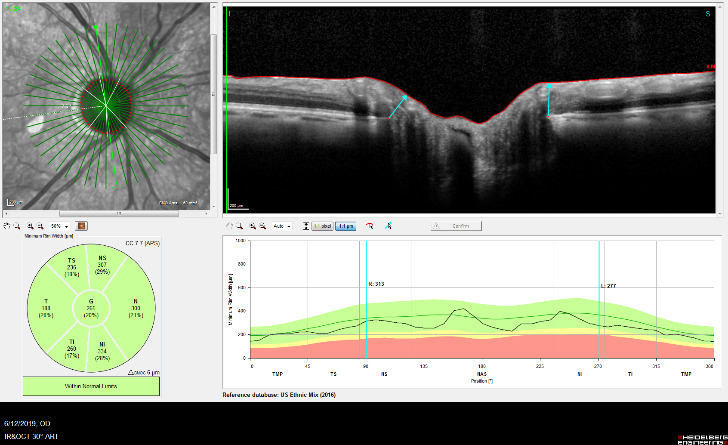

Optical Coherence Tomography (OCT) is an advanced imaging technology that has revolutionized the diagnosis and management of eye disease, especially glaucoma and retinal disease. OCT is a non-invasive method of imaging structures in the eye at an extremely high, microscopic resolution.

OCT uses infrared light to create cross-sectional, three-dimensional images of the tissues in the eye. As is the case for laser treatments, the eye is particularly amenable to imaging with OCT because the eye is optically transparent.

OCT Imaging of the Nerve Fiber Layer

OCT Image of the Retina

OCT is used in glaucoma to image the optic nerve and the nerve fiber layer in order to determine if there is damage from increased eye pressure. Because the resolution of OCT is so high, it can detect fine changes to the shape of optic nerve. Thinning of the nerve fiber layer is a sign that glaucoma is worsening and that the eye pressure is too high.

OCT Imaging of a Normal Optic Nerve

OCT Imaging showing a

Cupped Optic Nerve

Structural changes to the optic nerve or nerve fiber layer usually precede visual field loss. In many cases, 50% of the optic nerve can be damaged before visual field loss develops. As a result, OCT is a critical tool for diagnosing glaucoma at its earliest stages.

An example of an optic nerve with glaucoma damage imaged with both fundus photography and OCT and compared to the visual field in order to demonstrate the strucure-function relationship.

The lower half of the optc nerve has early damage, and this correlates with the small superior scotoma seen on the visual field test.